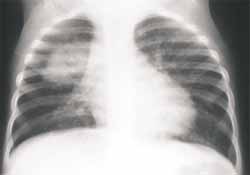

Además, este germen causa el mayor número de neumonías asociadas a derrame pleural y es el más aislado en casos de neumonías redondas9. El término de neumonía redonda se utiliza para describir un patrón de consolidación del espacio aéreo, esférico, usualmente no segmentario y frecuentemente posterior, que con alguna frecuencia puede verse en niños.

La mayoría corresponde a estadíos tempranos de consolidación y se cree que están relacionadas con el pobre desarrollo de vías colaterales en los niños (Figura 9). En ocasiones estas neumonías pueden confundirse con masas mediastinales o intraparenquimatosas, siendo la presentación clínica la clave del diagnóstico6-12

FIGURA 9. Proyección Ap de tórax en la cual existe neumonía redonda de localización parahiliar derecha.